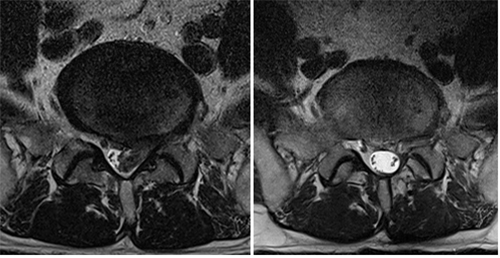

자기공명촬영

디스크의 구조와 척추뼈가 밀리면서 신경의 압박 상태, 관절, 인대의 비대로 척추관 협착 정도를 알 수 있습니다.